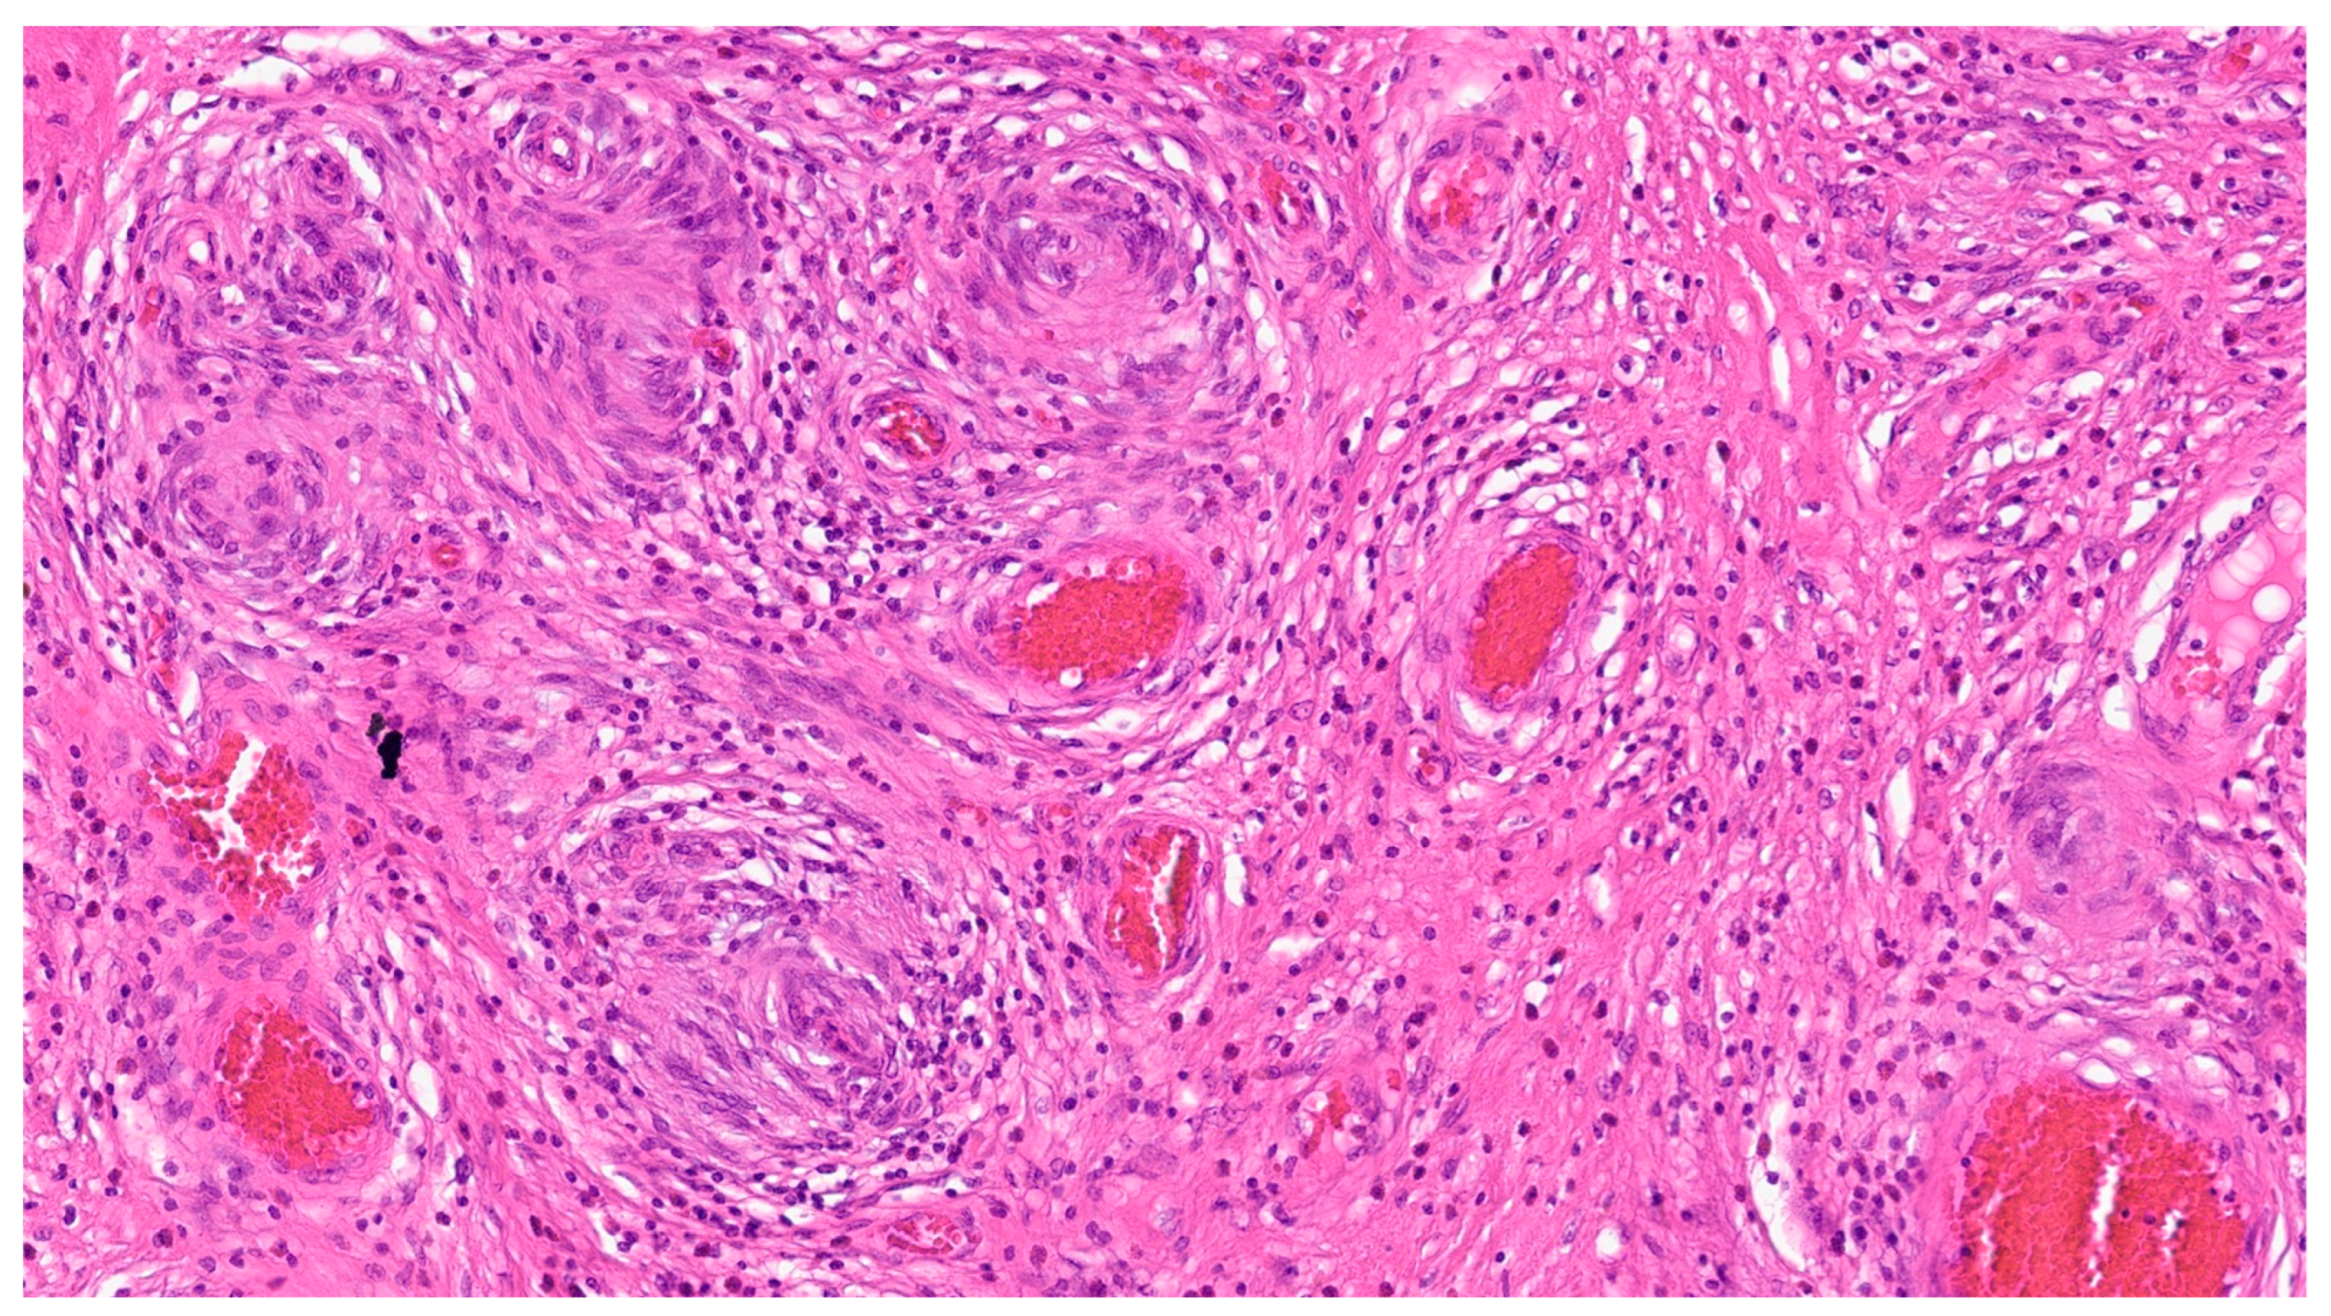

| Leiomyoma | Wide range of age | Esophagus, colon, and rectum | Asympromatic | Well-differentiated fascicles of bland, fusiform cells with elongated nuclei with tapered ends with eosinophilic cytoplasm | α-SMA, desmin, caldesmon |

| Leiomyosarcoma | Very rare in the GI tract | Small intestine | Abdominal pain, obstruction | Of fascicles of spindle cells with atypia, centrally placed cigar-shaped nuclei, and eosinophilic fibrillary cytoplasm with high mitotic counts | α-sma, desmin, caldesmon |